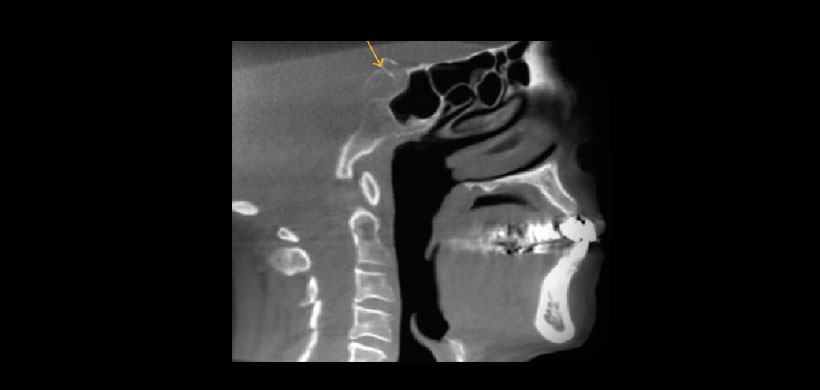

Fig 4. Tomografía volumétrica, vista sagital. Muestra hipertrofia adenoidea que produce el estrechamiento de la nasofaringe.